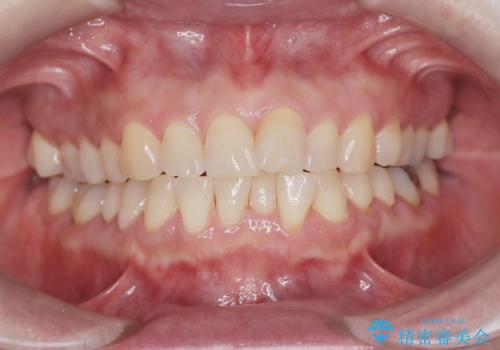

前歯の軽度なガタつきを、1年で美しく整える審美ワイヤー矯正

- 前歯の軽度なガタつき(叢生)を気にされてご来院されました。精密な検査の結果、抜歯は不要で、わずかなスペースを確保することで歯並びを整えられると診断。患者様のご希望と状態に合わせ、目立ちにくい審美ブラケットを使用したワイヤー矯正による治療計画を立案しました。スペース確保は、奥歯を少し後ろへ動かす遠心移動と、歯の側面をわずかに削る**IPR(歯間乳頭保護下ストリッピング)**を併用し、約1年間での治療完了を目指しました。

ワイヤー矯正ならではの確実な歯のコントロールにより、当初の計画通り約1年という短い期間で、前歯のガタつきが解消。見た目が美しく整っただけでなく、清掃しやすい機能的な歯並びを獲得していただけました。